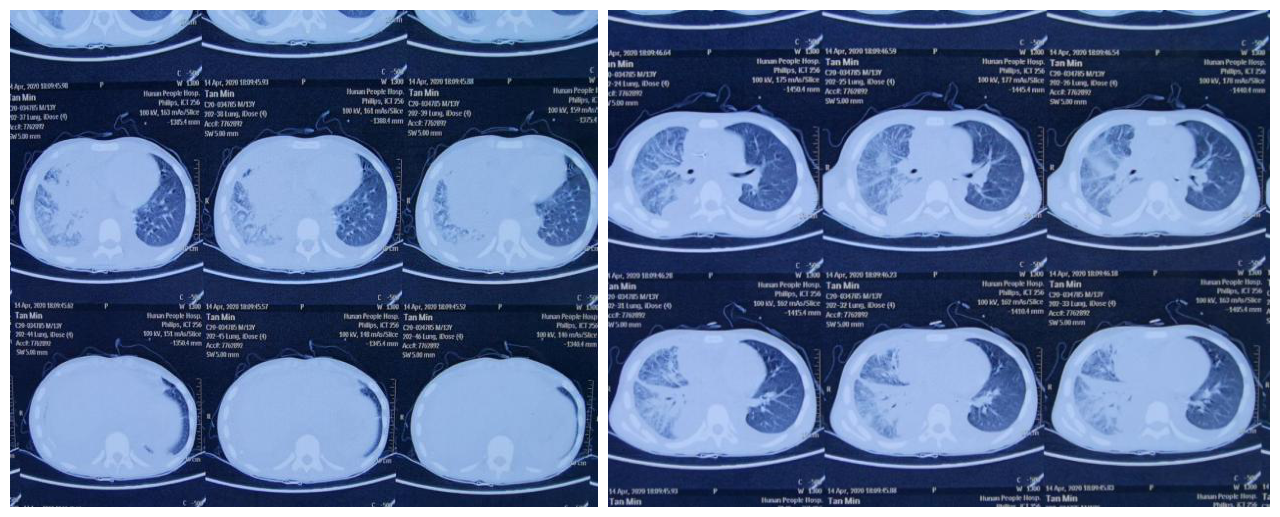

1岁8个月的小欣怡近3个月因反复咳嗽多次在当地住院治疗,体重不增,近半月咳嗽加重,并伴有气促发绀入住儿三科。急查肺部CT提示双肺多发磨玻璃密度影,予以呼吸机辅助通气后症状无明显改善。为明确病因,儿三科团队给孩子行纤维支气管镜探查,心胸外科张志功副主任医师在单孔微创胸腔镜下行肺活检术,并完善基因检查。针对各项结果,钟礼立主任与病理科李艳春、钟仁华、影像科毛志群、成人呼吸科赵飞及外院电镜室王俊普等多名专家会诊后确诊患儿为非常罕见的ABCA3基因异常脱屑性间质性肺炎,并对孩子后期的治疗,制定了详细周全的方案。就这样,这个外院宣布“治愈希望渺茫”的孩子经过2个多月的治疗,肺部CT明显改善,气促发绀症状都在慢慢好转。